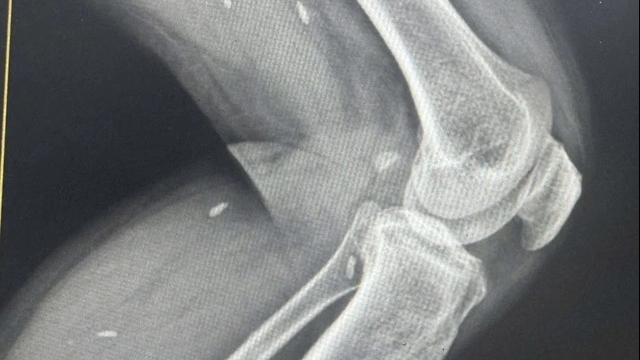

![]() |

| Hình ảnh phim chụp tổn thương sọ não và xoang ở bệnh nhân nhiễm nấm đen |